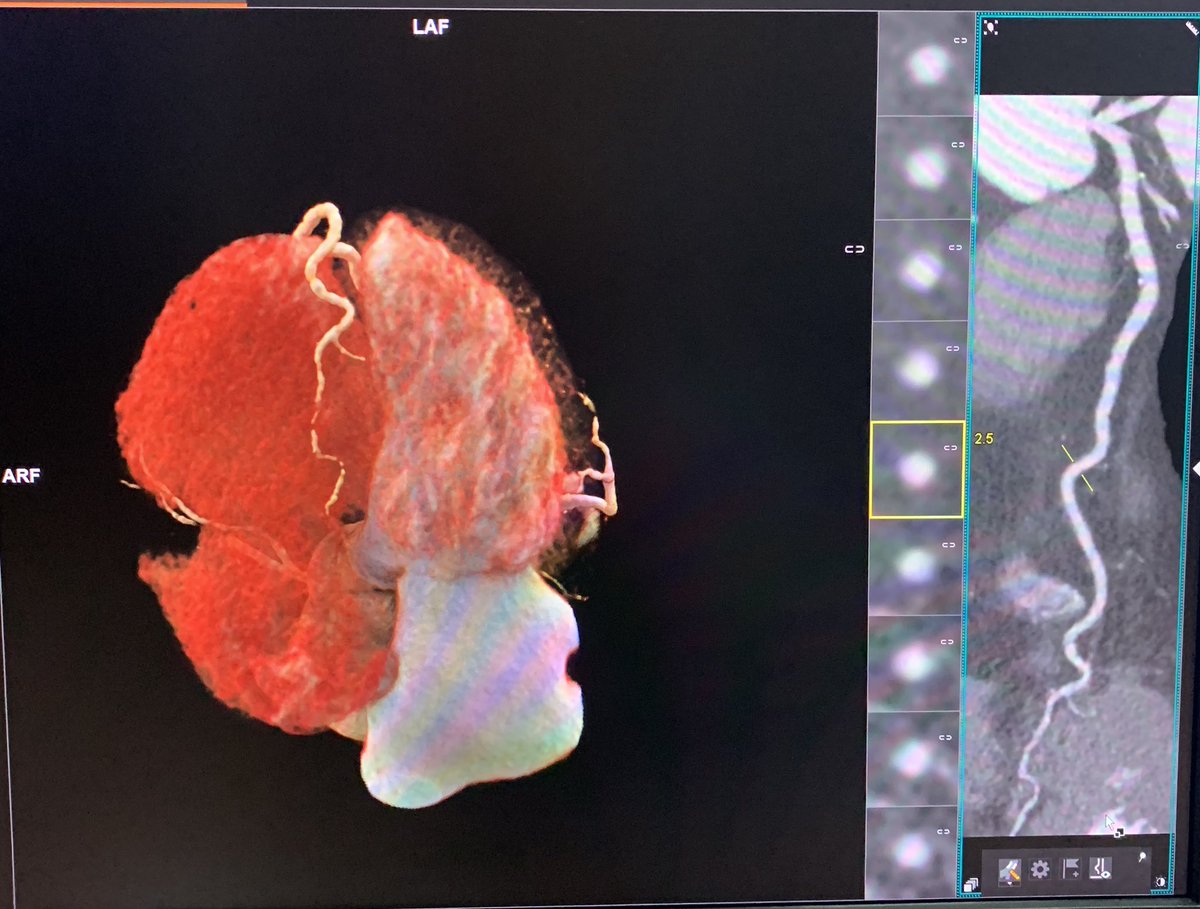

33 - Daniel Campuzano Corazón artificial ¿Qué obtenemos de una Inteligencia-Artificial, al mostrarle una reconstrucción volumétrica por angiotomografía de un corazón con ALCAPA...? ¿Cómo lo entendería? #imagenmasbella23